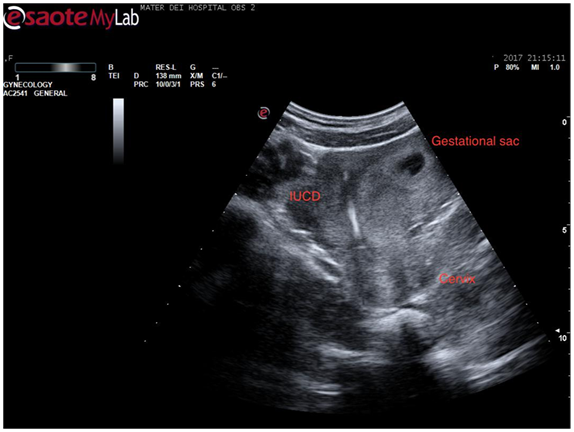

Returning to the sagittal view of the uterus the entire uterus was visualized and on sliding the probe across the uterus in this plane, the intrauterine contraceptive device came clearly into view (Figure 3). This was quite a dramatic view as the whole intrauterine device was seen to be placed inside the body of the uterus. The patient became visibly anxious at this stage so care was taken to reassure her and explain the findings thus far. By sliding the probe again an image was obtained showing both the coil and the gestation sac in the same view which confirmed that this was a case of pregnancy with a coil in situ (Figure 4).

Figure 3 Sagittal view of the uterus with coil seen in its entire length within endometrial cavity.

Figure 4 Sagittal view of the uterus showing both coil and gestation sac.